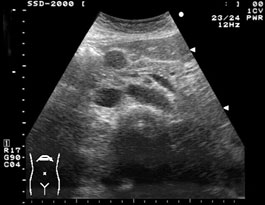

腹腔内には、他にも多数の腫大したリンパ節が認められた. 矢頭は上腸間膜節(#14)である. 消化肝癌における転移性リンパ節腫大の検索は、腫瘍の広がりを知る上で重要である. |